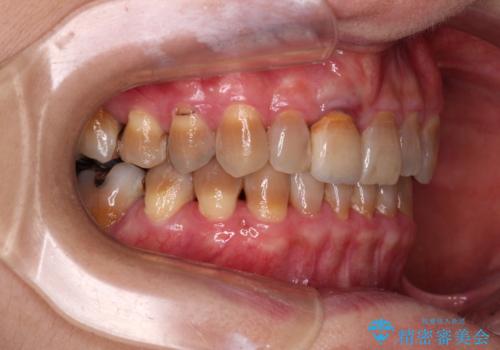

- 前歯のデコボコと、顎に負担のかかる歯並びを改善したいとのことで来院された患者様です。

うまく歯ぎしりができず、強く食いしばりをしてしまう咬み合わせであったため、奥歯に非常に負担がかかっていました。

インビザラインを用いて前歯のデコボコを改善するとともに、奥歯の咬み合わせを変えてスムーズに歯ぎしりできるように排列していくこととしました。